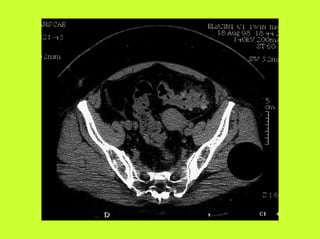

3) RADIO (PNO)

RADIOGRAPHIES

ABDOMEN SP -scanner

PNEUMOPERITOINE SUR SUJET DEBOUT

" Croissant gazeux sous diaphragmatique

" Disparition du niveau hydroaérique gastrique

PNEUMOPERITOINE SUR SUJET COUCHE

" Visibilité du ligament triangulaire du foie

" Visibilité anormale des parois intestinales

" Image aérique pré-hépatique

"Pneumatisation de MORRISSON

(cul de sac inter-hépato-rénal)

AUTRES EXAMENS

"TOGD aux hydrosolubles?

" Echo, scanner

" Coelioscopie ?

" Pas de lavement colique, pas de fibroscppie, pas de coloscopie, pas

d’IRM